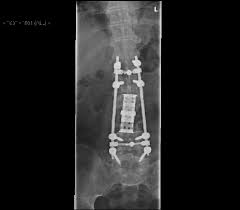

41+ reasons for chordoma cancer life expectancy: Doctors estimate chordoma survival rates by how groups of people with chordoma have done in the past. The rest are found along the spine. Chordoma happens most often in adults between 40 and 60, though it can happen at any age. Treatments for chordoma include surgery, chemotherapy, and radiation therapy. About 57% of the patients were alive after 10 years and, in about 44%, the tumor did not get worse. Chordoma tumor cells arise from cells of the notochord the tissue in a fetus that acts as the building blocks for the spine. Chordomas are generally slow growing and are most commonly found within the head at the base of the skull near a bone called the clivus and in the lower portion of the spine.

Treatments for chordoma include surgery, chemotherapy, and radiation therapy.

Symptoms of chordomas can include back pain, numbness, headaches, and vision problems. The average bone cancer life expectancy for a chordoma is around 7 years after diagnosis. This is because they can be hard to diagnose and treat. 41+ reasons for chordoma cancer life expectancy: 31+ chordoma cancer life expectancy pictures. Chordoma chordoma is a cancerous bone tumor, often located along the spine or at the skull base. Implementation of treatment can prolong the life of patients for up to five years. Chordomas grow slowly, gradually extending into the bone and soft tissue around them. The life expectancy for people with a chordoma depends on their age, the type of the tumor, the size and location of the tumor, and other factors. About 30% occur in the skull base, the area behind the eyes and nose that slopes down to form the floor of the skull. About 300 people are diagnosed with chordoma in the. These include the nerves that control. This type of tumor has a high recurrence rate.